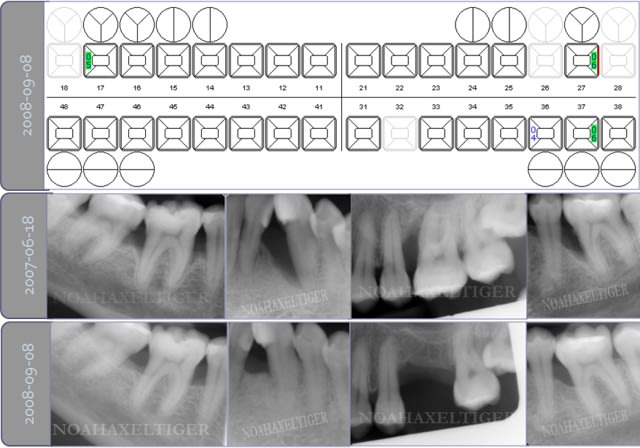

> voila comme promis les 2 cas cliniques.

>

> patiente 1 : paro aggressive, importantes lésions

> angulaires traitées par emdogain sauf mesial 33 où

> j'ai préféré faire une GTR avec comblement

> BioOss.

Superbes résultats !

Quelques questions :

1 La conservation de la 28 n'est elle pas un facteur défavorable ?

2 la 26 a t'elle été extraite en première intention ou après un échec de la régénération ?

3 avais tu dans ce cas une espèce bactérienne spécifique ?